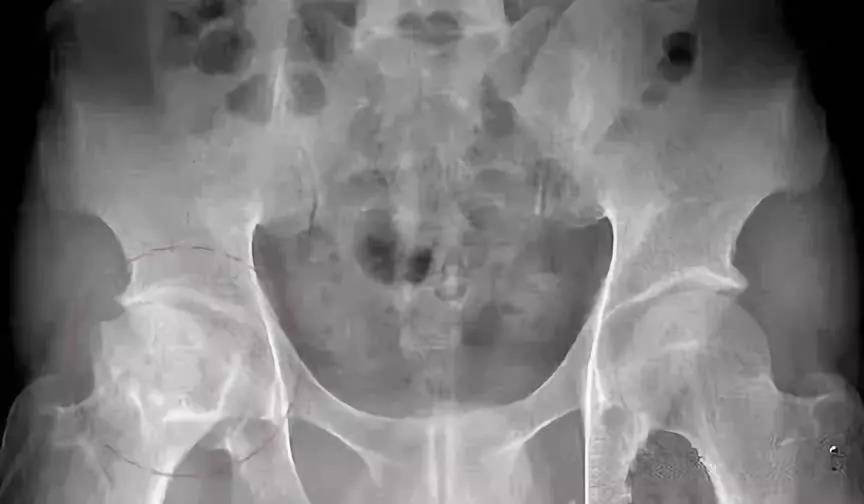

(2)股骨头坏死CT的表现

Ⅰ期

骨质无明显异常,但可有滑膜增厚,关节囊肿胀,关节腔积液,关节间隙相对增宽。

Ⅱ期

股骨头形态正常无塌陷,正常时股骨头中心因持重应力的作用骨小梁生理性密度增高呈“星芒征”,当发现骨缺血性坏死时,星芒状骨纹间骨小梁吸收呈不均匀大眼状,由于反映性增生,使星芒状骨纹增粗、扭曲、浓密。

Ⅲ期

此期称为塌陷前期,股骨头变平,股骨头前上部关节面下见窄细状透亮带,即“半月征”。

Ⅳ期 股骨头塌陷变形,股骨头内是不同程度囊变,周围有硬化或不规则,因塌陷所致的浓度区,可见碎骨片和关节游离体。继发退行性骨关节病,出现增生骨刺、关节间隙狭窄、关节半脱位。

上图为IV期